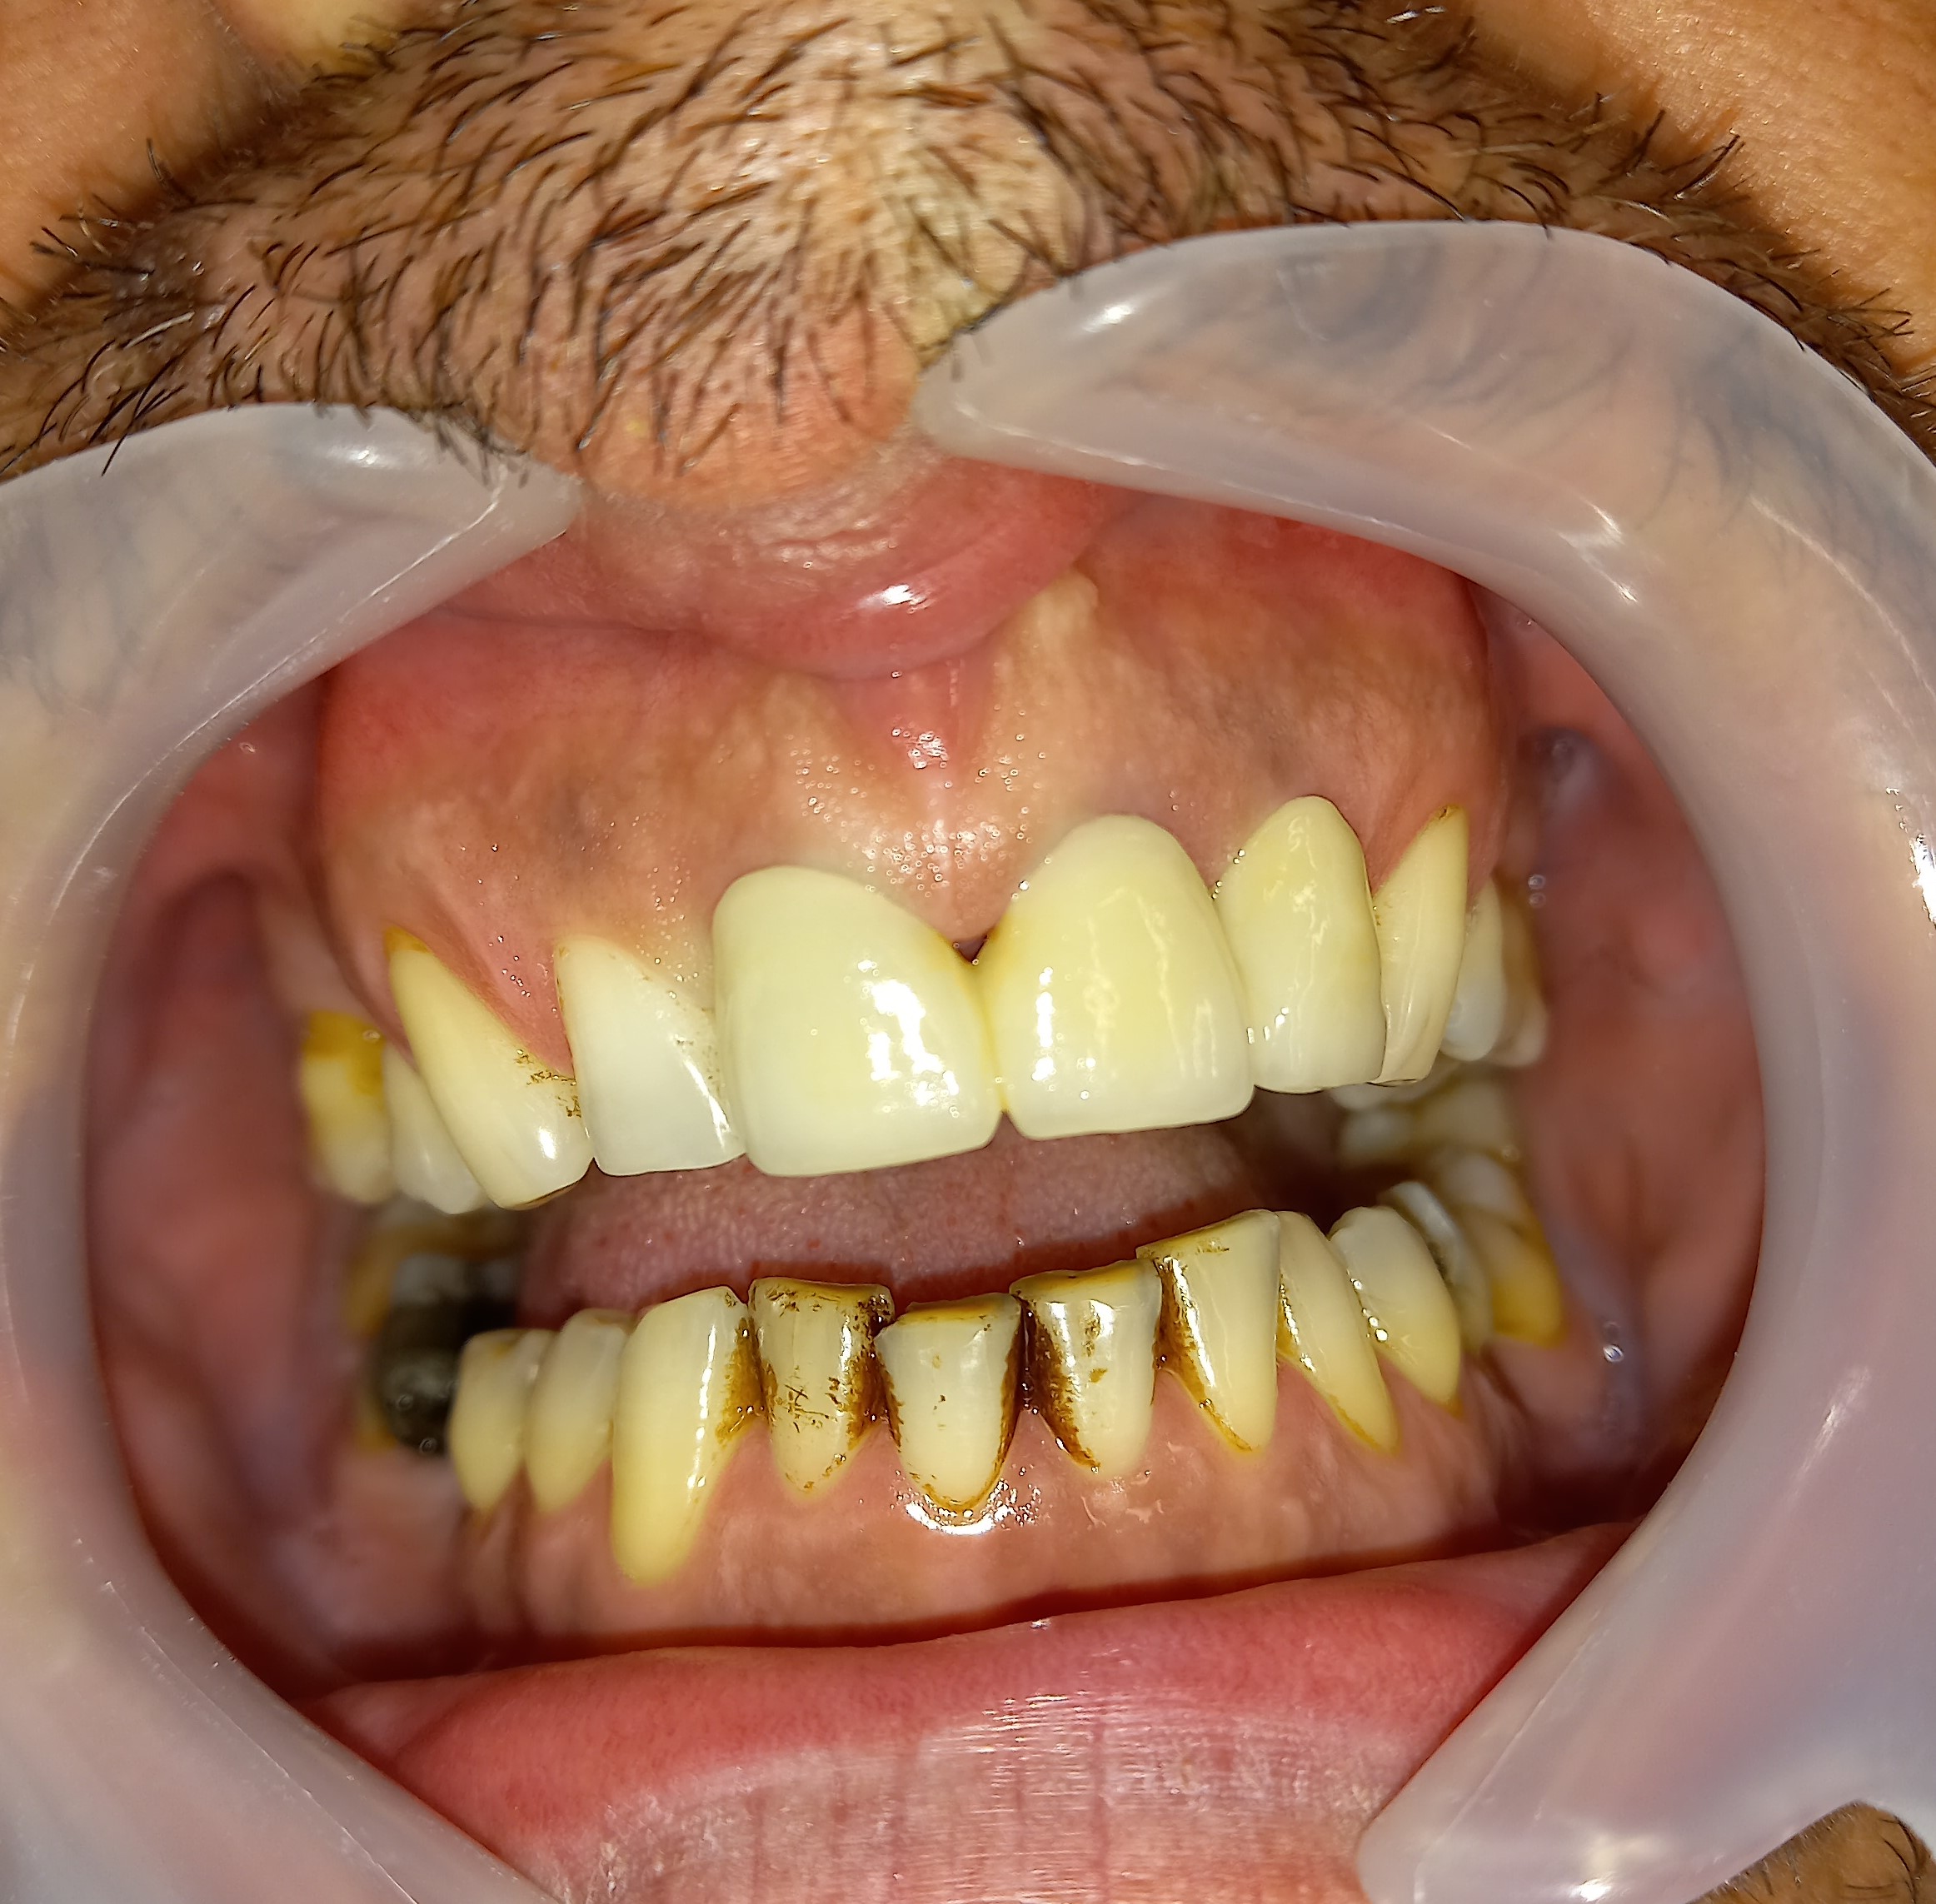

Η σημασία της προσωρινής αποκατάστασης κατά τη διάρκεια προσθετικής εργασίας